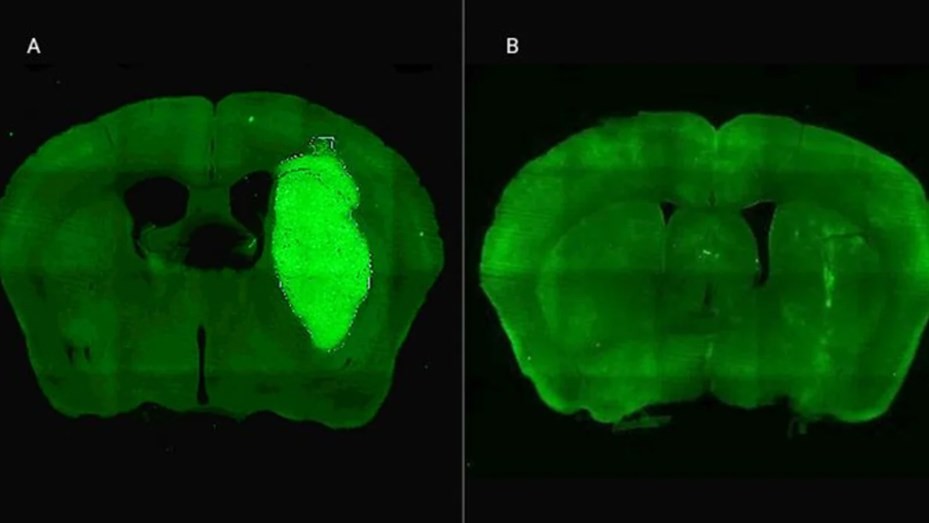

Candolfi y colegas utilizaron una terapia génica experimental basada en una molécula muy pequeña o péptido llamado P60, desarrollado por Juan José Lasarte en la Universidad de Navarra, en España, que atraviesa la membrana celular e inhibe la proteína Foxp3. “Cuando en experimentos de laboratorio bloqueamos Foxp3 utilizando P60, la respuesta de las células de glioblastoma a la radioterapia y a una variedad de drogas quimioterapéuticas mejoró notablemente”, destacó la investigadora del CONICET.

Además, P60 tuvo efectos antitumorales directos, reduciendo la viabilidad y la migración de las células de glioblastoma e inhibiendo la proliferación de células endoteliales que son clave para la progresión del tumor. Para evaluar estos efectos, los autores del estudio utilizaron una variedad de modelos celulares murinos (de roedor) y humanos. “En particular, los cultivos derivados de biopsias de pacientes con glioblastoma desarrollados por nuestro colaborador Guillermo Videla Richardson, del Instituto FLENI, son muy útiles para representar la heterogeneidad de estos tumores”, indicó Candolfi.